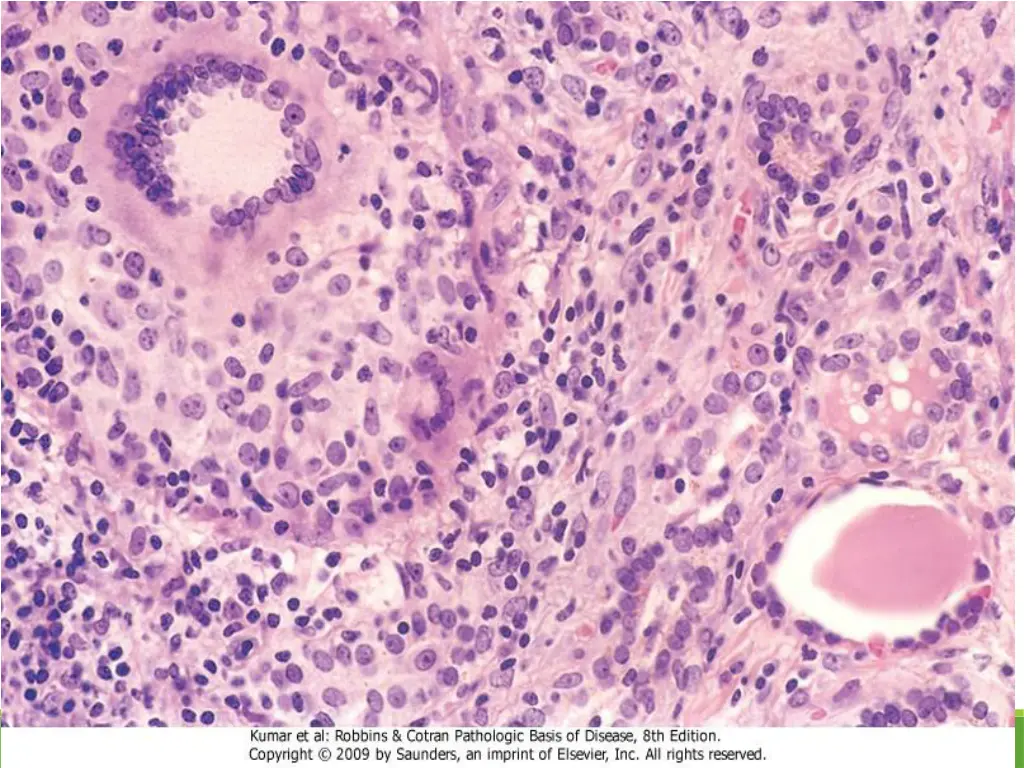

21. Hashimoto Thyroiditis, Morphology The thyroid is often diffusely enlarged The cut surface is pale, yellow, tan, firm and somewhat nodular. Microscopic examination reveals extensive infiltration of the parenchyma by a mononuclear inflammatory infiltrate containing small lymphocytes, plasma cells, and well-developed germinal centers The thyroid follicles are atrophic and are lined in many areas by epithelial cells distinguished by the presence of abundant eosinophilic, granular cytoplasm, termed H rthle cells.

22. Hashimoto Thyroiditis